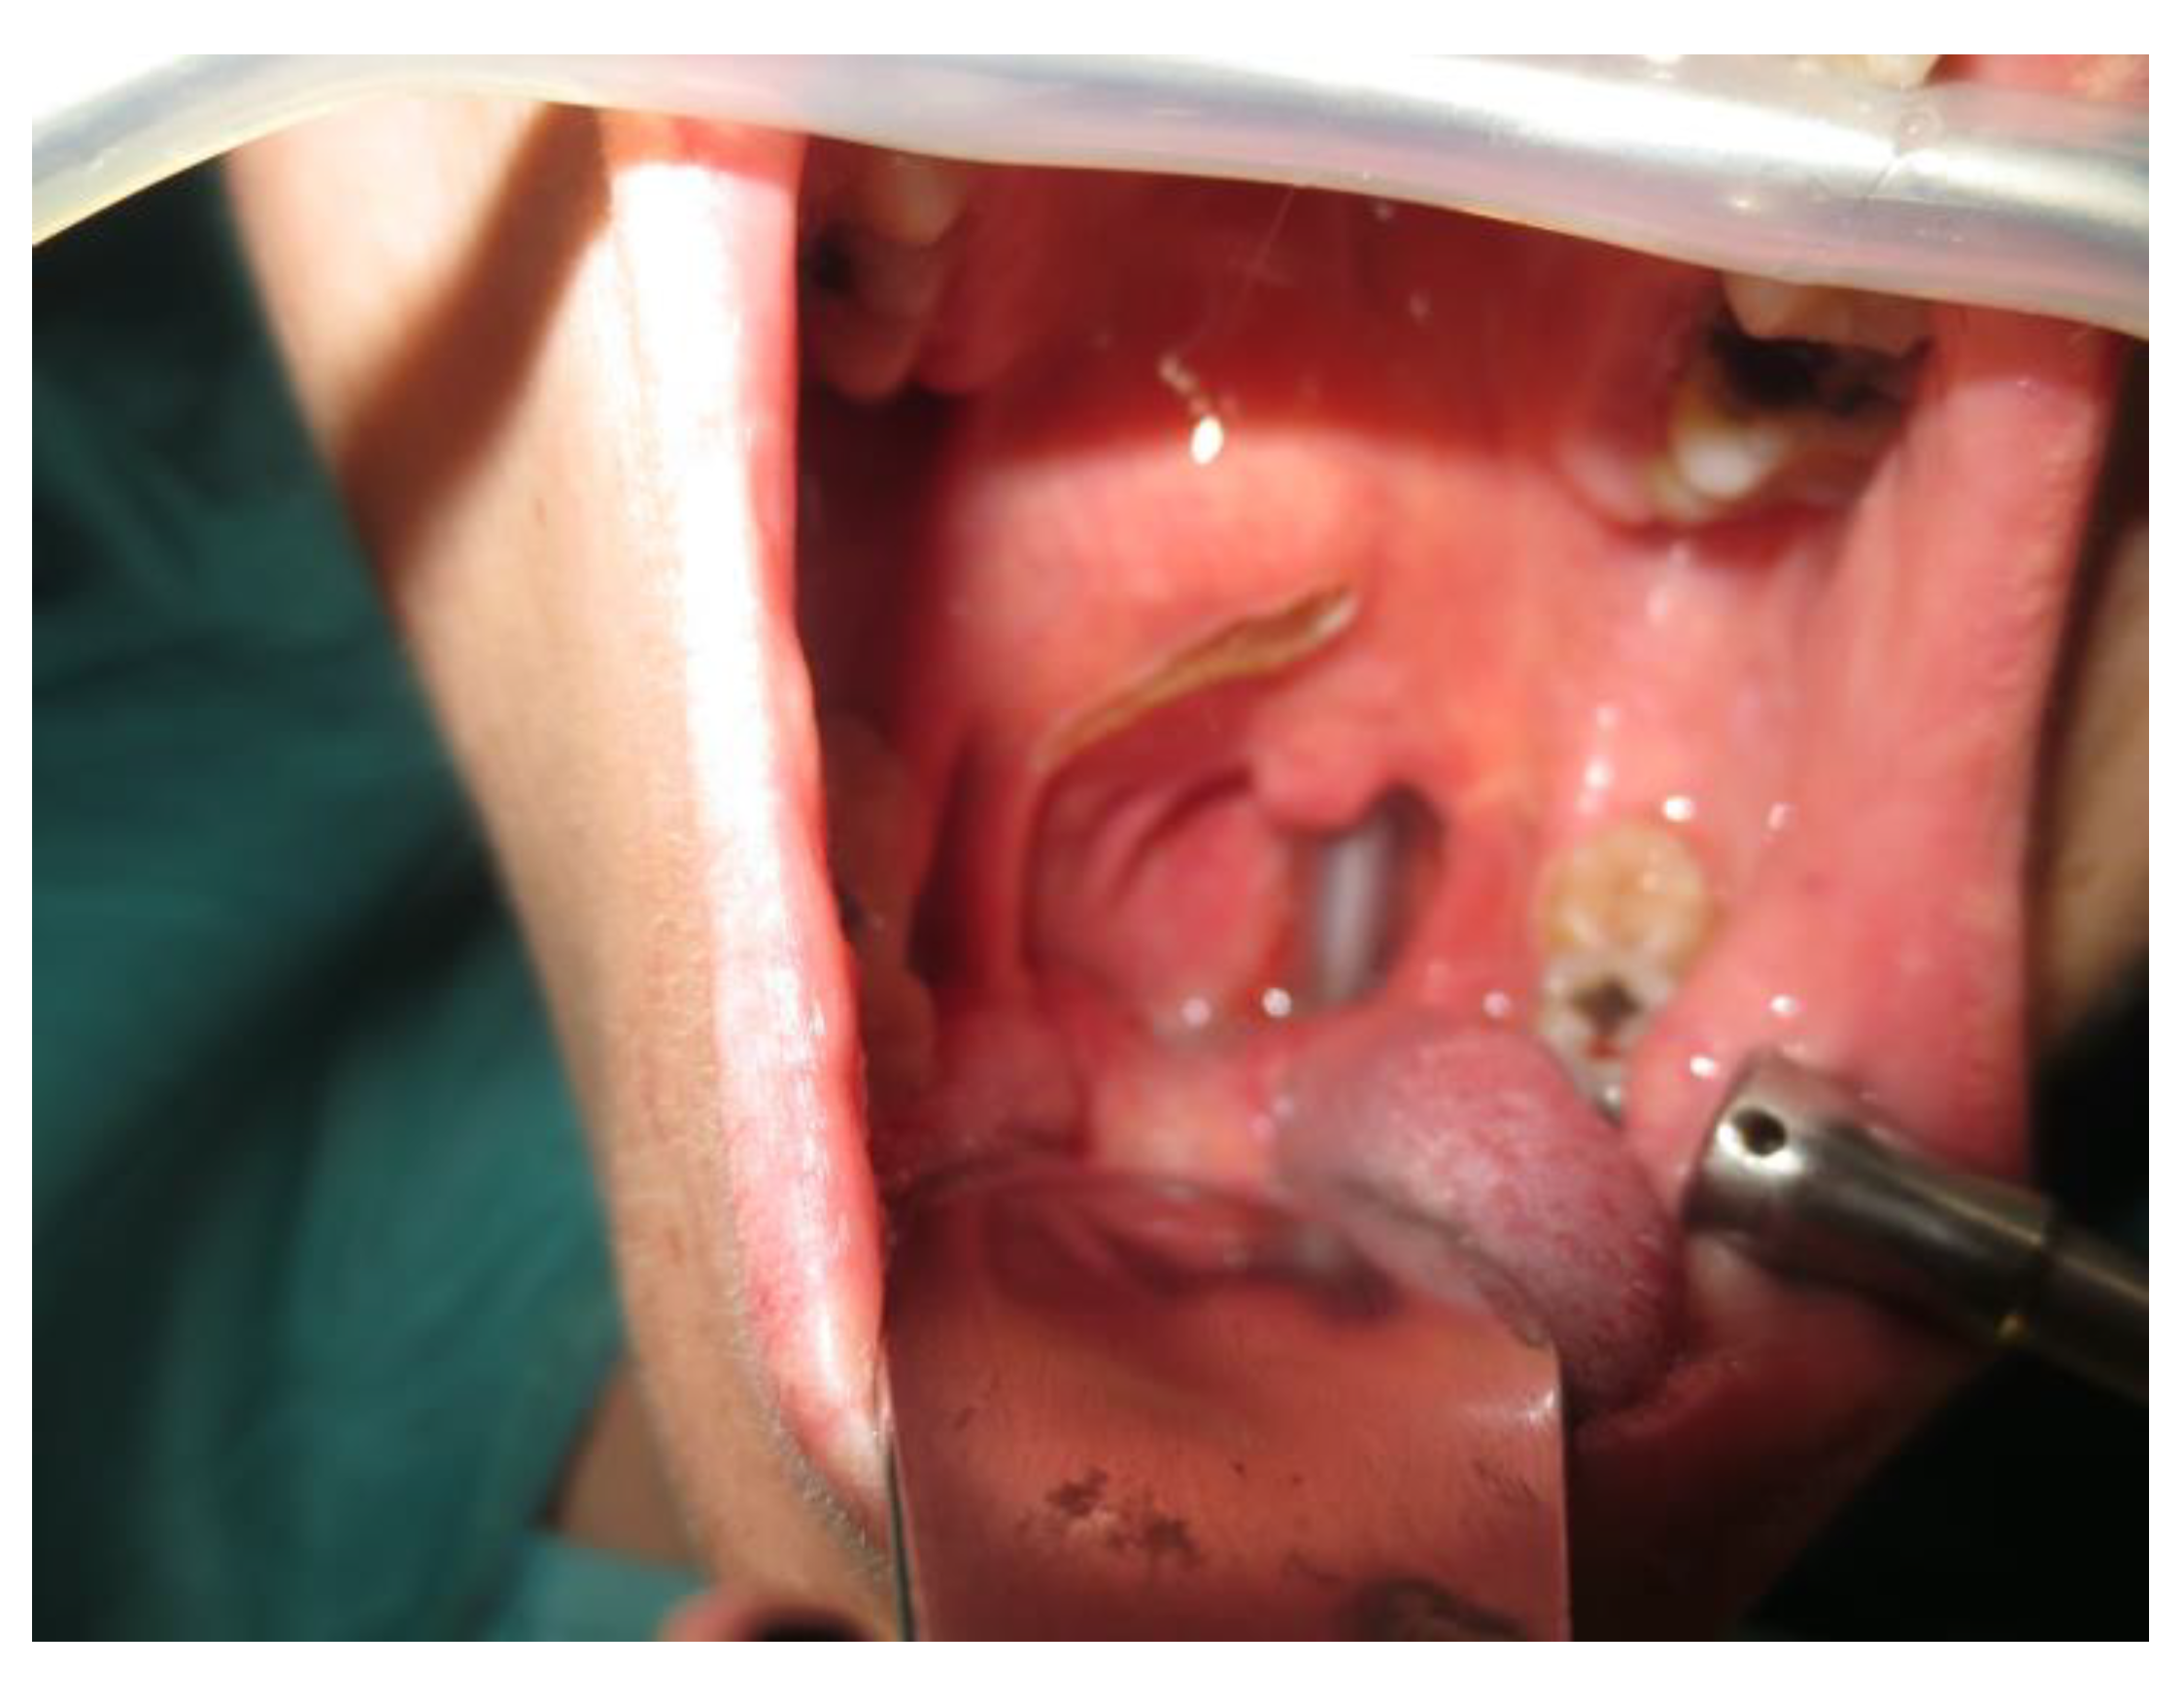

- Two schwannomas (Figure 5) originating from the cervical sympathetic chain and that arose in the superomedial aspect of the PPS, medially to the carotid sheath. The first patient underwent surgery in 2008, the second in 2019. No complications were observed during surgery and no tumour recurrence has been observed after 14 and 4 years, respectively. The only long-term complication observed was Horner syndrome (Figure 6), despite the continuity of the nerve not being interrupted. The hospitalisation time was three days for both patients.